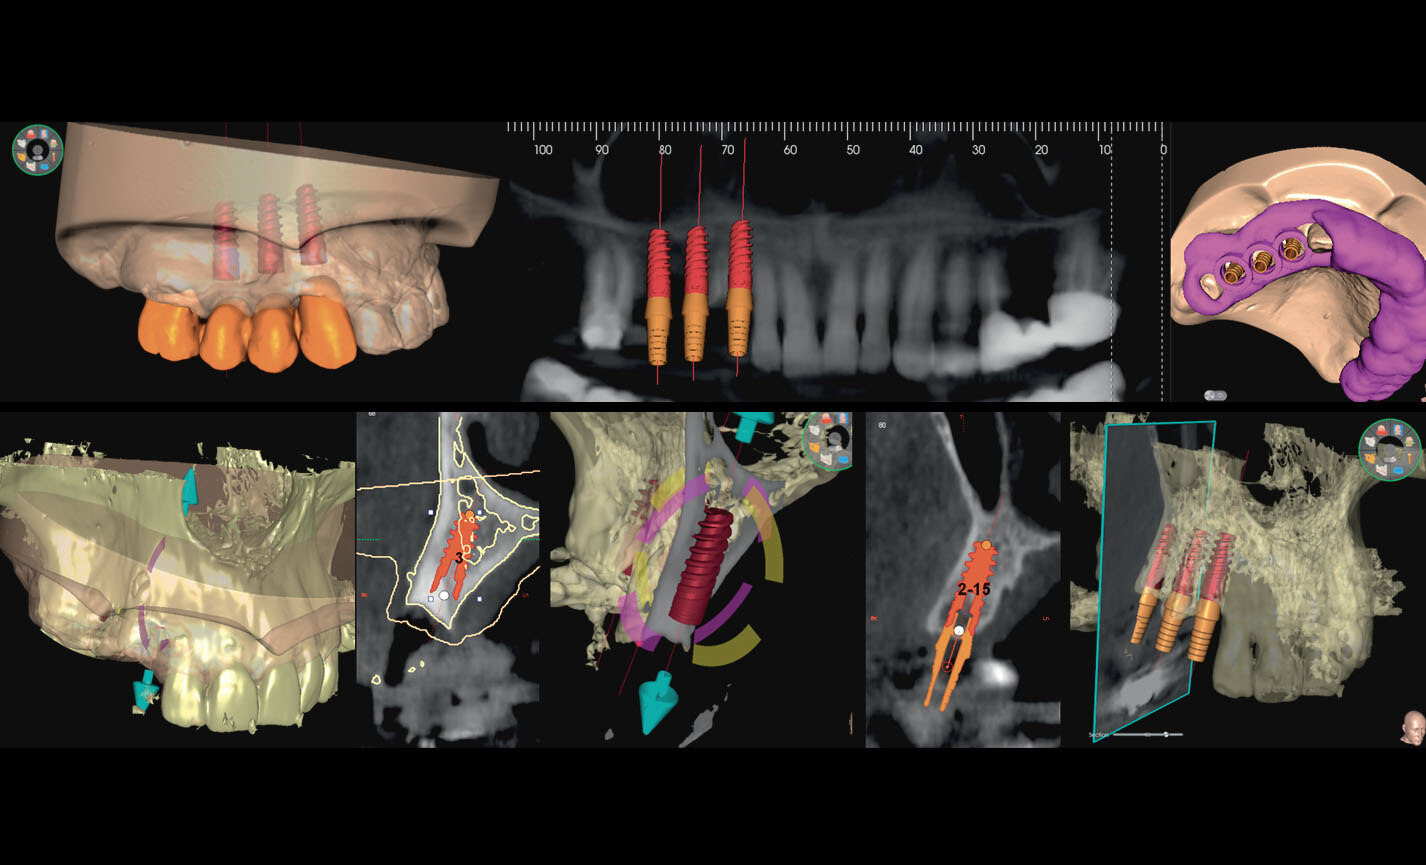

Planification implantaire avancée

Définissez la position de l’implant directement sur le modèle 3D, combinez-le avec les données STL provenant de scanners intra-oraux, et déterminez le projet prothétique définitif. Avec les instruments de planification implantaire avancée, vous pourrez opérer en toute sécurité, grâce aux informations précises sur la quantité d’os et la distance par rapport aux structures anatomiques avoisinantes, comme le canal mandibulaire, en définissant une distance minimale de sécurité.